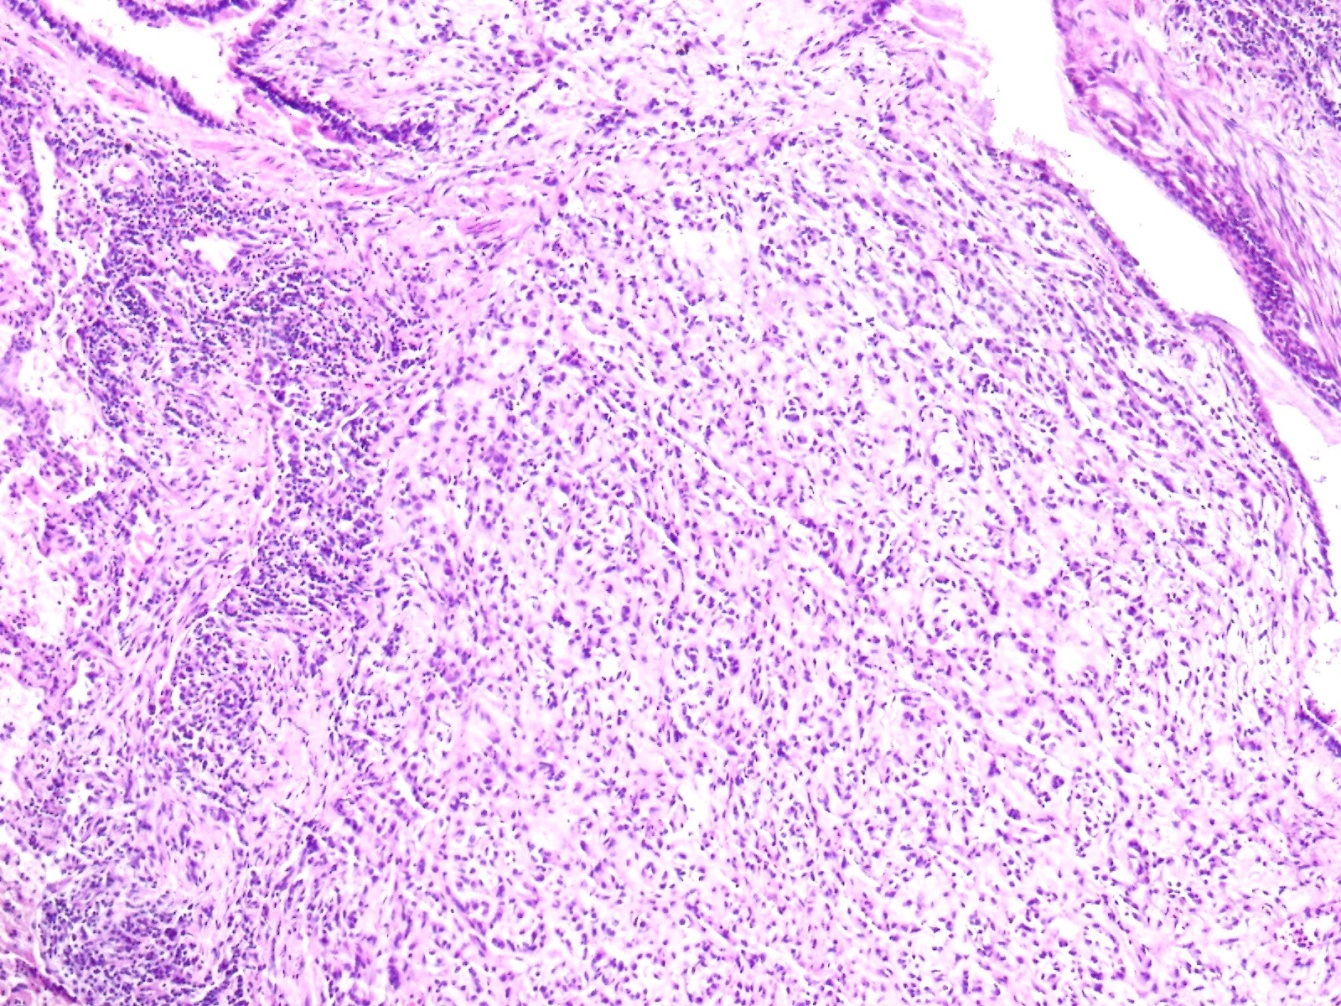

The tumor was a solitary, endobronchial, well-circumscribed mass with a fleshy uniform white and gelatinous cut surface that measured 2x1.7x1 cm. histologically, the tumour was multinodular, and its cells were small, ovoid or polygonal with vesicular nuclei resembling chondrocyte-like or physaliferous cells in a background of myxoid stroma (Figure 2). There were infrequent mitotic figures, as well as extensive lymphoplasmacytic cell infiltration (Figure 3).

Frozen sections revealed spindle cell proliferative lesions with a rich mucoid background and a significant lymphocyte and plasma cell infiltration. It was impossible to tell if it was benign or cancerous. The tumor cells were distributed in a nodular pattern with considerable collagen interstitium, according to H&E staining. Tumor cells were spherical and oval, organized reticularly or ribbon-like in a mucoid background (Figure 2,3). Tumor cell atypia was mild to moderate. Mitotic activity was less than 2/10 HPF (high-power fields). The tumor had a mucinous background, many lymphocytes and plasma cells in the infiltrate, and many spindle cells proliferated (Figure 4).